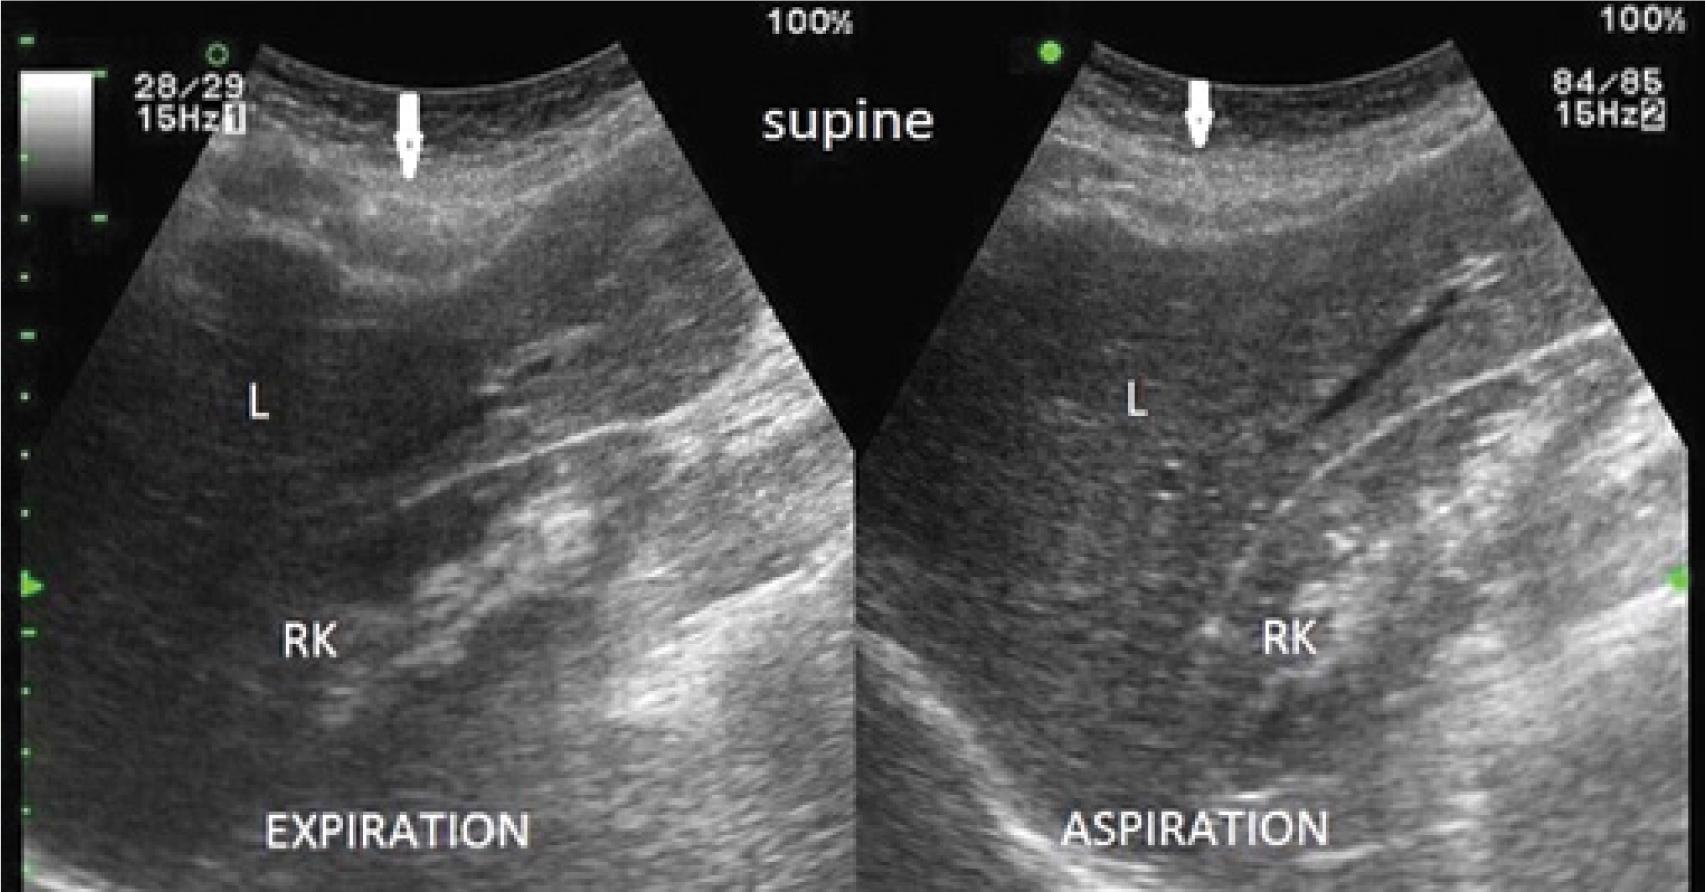

Fig. 1